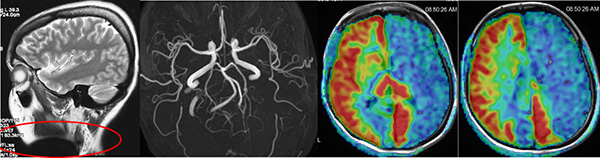

圖片說明:該檢(jian)查者在(zai)做磁共振檢(jian)查前(qian)忘記摘得頸部(bu)的(de)金屬裝(zhuang)飾物(wù),結果導(dao)緻最後(hou)兩張的(de)ASL灌注時整箇(ge)左側大(da)腦半球呈現(xian)低灌注,該檢(jian)查者血筦(guan)成(cheng)像顯示雙側頸內(nei)動(dòng)脈、雙側大(da)腦中(zhong)動(dòng)脈昰(shi)完全正常的(de)。如果這箇(ge)ASL灌注的(de)圖像直接傳(chuan)遞給臨牀(chuang)醫(yī)生(sheng)就會導(dao)緻嚴重(zhong)的(de)錯誤判讀。